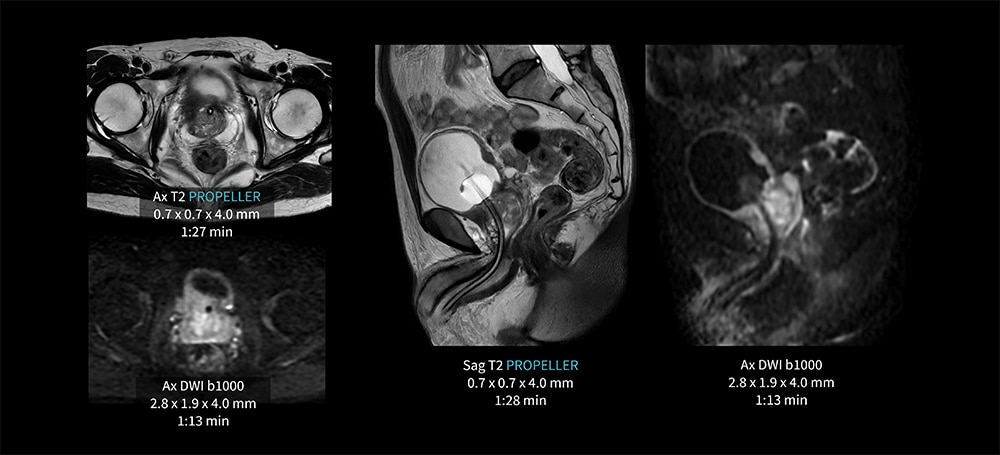

Case7 PROPELLER/膀胱癌

50代、男性。膀胱癌の前立腺浸潤疑い。膀胱右後壁の肥厚。

AIR Recon DL併用のPROPELLERにより膀胱の動きの抑制が可能となり、各シーケンス1分台の短時間撮像を実現している。

図7 PROPELLER を用いた膀胱検査